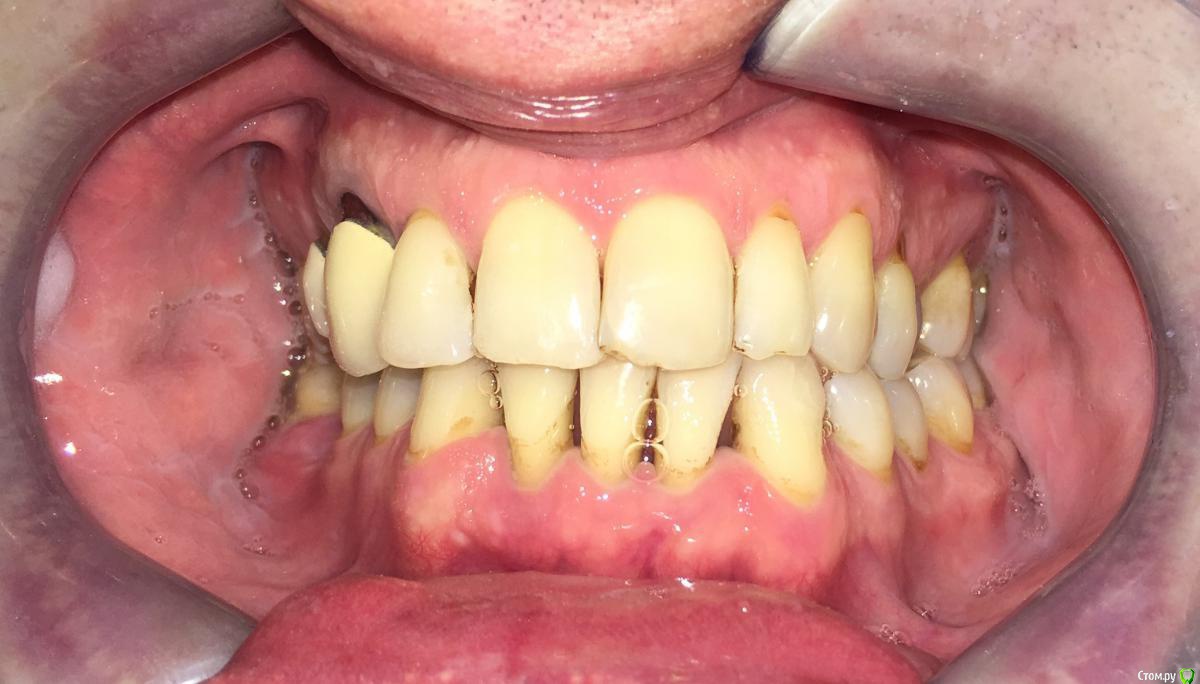

Nitrino1 Опубликовано 20 января, 2018 Поделиться Опубликовано 20 января, 2018 Коллеги помогите поставить правильный диагноз и составить план лечения, чтоб продолжительно держалосьОбъективно на всех зубах камни над и поддесневые. В 47ом зубе 3-я степень подвижность.Почистил все камни и налеты, назначил полоскание, пасту Парадонтах, удалил 47ой зуб.Сделал панорамку (до удаления) и фотки тоже до удаления.Должен составить план лечения... Ссылка на комментарий

red_butler Опубликовано 21 января, 2018 Поделиться Опубликовано 21 января, 2018 Хронический генерализованный пародонтит тяжелой степени, в ремиссии (по МКБ-10 Хронический генерализованный пародонтит, код К0531) Ссылка на комментарий

Nitrino1 Опубликовано 21 января, 2018 Автор Поделиться Опубликовано 21 января, 2018 Хронический генерализованный пародонтит тяжелой степени, в ремиссии (по МКБ-10 Хронический генерализованный пародонтит, код К0531)какой план лечения вы бы порекомендовали? интересует момент с нижними резцами, их шинировать или же удалить? на верхних 6ках тоже ситуация не очень. Вообще какую тактику выбрали бы?И еще просьба, посоветуйте что можно почитать современное на тему парадонтитов и парадонтозов, то что у меня есть это старое уже Ссылка на комментарий